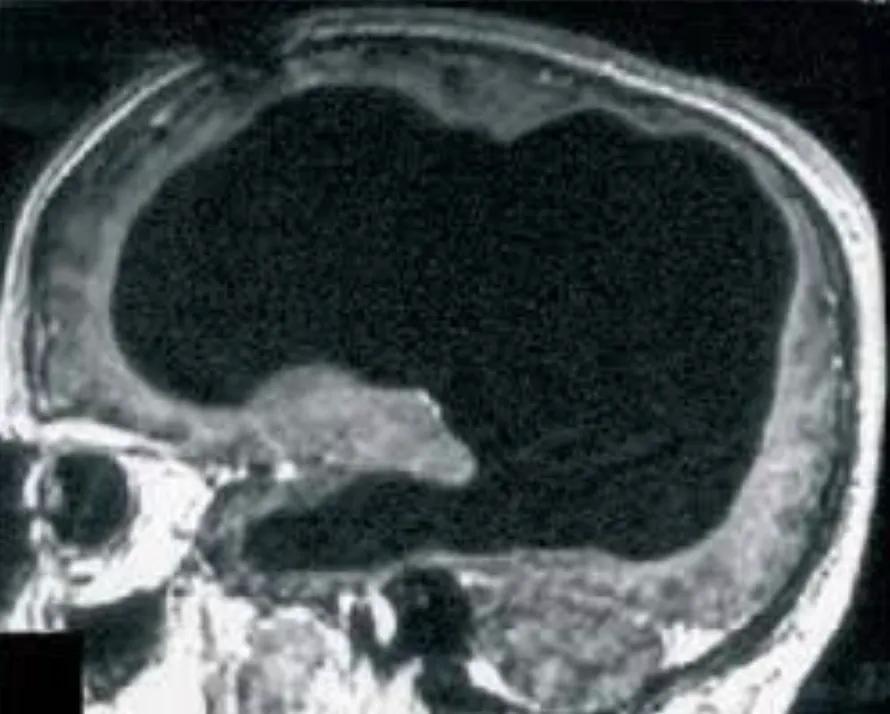

2007年《柳葉刀》報道的那位法國男子,雖然腦室急劇擴張,但這實際上是慢性腦積水造成的物理壓縮。

他的大腦皮層並未消失,而是被壓成了一層薄紙貼在顱骨上(下圖),如同被壓扁的三明治,結構依然完整,神經連接依然存在。這證明的是大腦驚人的可塑性。

圖源:柳葉刀

而亞歷克斯的情況截然不同,她是真正的“缺失”,她的神經元不是被壓縮,而是被液化吸收殆盡。因此,亞歷克斯的生存比那位法國公務員更具顛覆性,她證明了人類可以在沒有皮層“硬件”的情況下,依然維持某種形式的“軟件”運行。